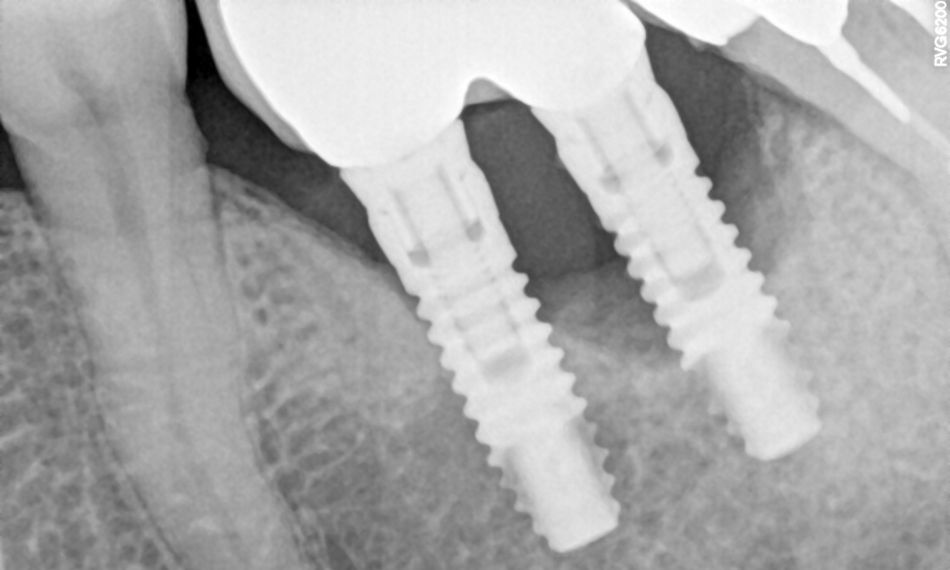

The radiographic examination revealed both horizontal and vertical bone loss around the implants, particularly around implant #37 (Fig. 1).

Fig. 1